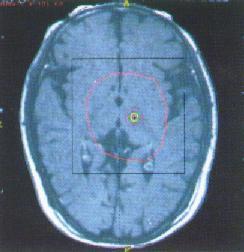

③功能影像學檢測:採用PET或SPECT用特等的放射性核素檢測,疾病早期可顯示PD患者腦內DAT功能顯著降低,D2型受體活性在早期超敏,後期低敏,DA遞質合成減少;對PD早期診斷、鑑別診斷及監測病情進展有一定價值;

①蒼白球或丘腦底核毀損或切除術:丘腦手術對震顫有效,蒼白球手術對運動遲緩有效;瀰漫性腦血管病為手術禁忌症;

②腦深部電刺激:刺激靶點主要是丘腦底核和蒼白球,原理是糾正基底節過高德意志性輸出以改善症狀;使適用於藥物治療失效、不能你受或出現異動症狀者,對年齡較輕,症狀以震顫、強直為主且偏於一側者效果較好,術後仍需藥物治療;